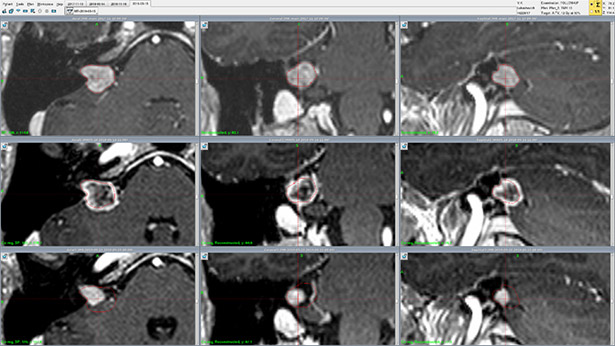

На рисунке показано рабочее окно контроля. Снимки представлены в трех плоскостях: аксиальный, фронтальный, сагиттальный. У данного пациента проводилось лечение и 2 контроля, красным контуром показан первичный объем облучаемой опухоли (акустическая невринома).

На рисунке (верхняя строка) показан снимок, по которому проводилось планирование. Первоначальный объем опухоли составлял 823,7 мм3, размер 14,3×9,5×11,6 мм.

При первом контроле через 6 месяцев (средняя строка) объем опухоли составил 1,03 см3, а размер 17,0×10,2×12,5 мм. Увеличение размера и объема, или псевдопрогрессия, обусловлено реакцией опухоли на РХ – постлучевым патоморфозом.

На втором контроле через 18 месяцев после радиохирургии (нижняя строка) хорошо видно значительное уменьшение опухоли: объем 255 мм3, размер 10,5×6,3×5,3 мм. Таким образом, объем опухоли уменьшился в 3,2 раза по сравнению с начальным.

Верхний ряд – МРТ-сканы во время радиохирургии. Средний ряд – МРТ-сканы первого контроля. Нижний ряд – МРТ-сканы второго контроля. Левый столбец – аксиальные срезы. Средний столбец – фронтальные срезы. Правый столбец – сагиттальные срезы.